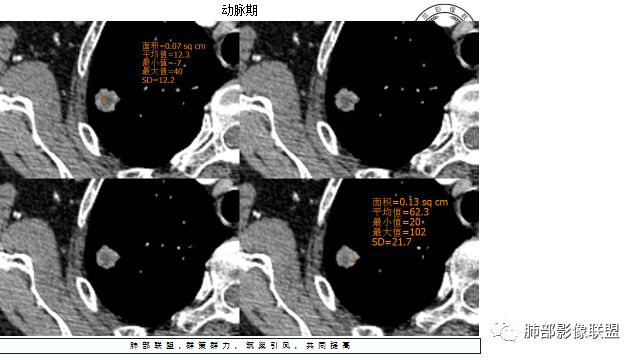

4.增强扫描成明显环形强化,中央液化坏死,内壁清楚且较为规整。

分析:

1.肺鳞癌是容易坏死,但如此小的结节出现影像明显可见的坏死区,且内壁如此清楚规整,我们临床实践中肿瘤非常少见,重要的事情说三遍!!!

病灶缺乏典型的分叶且明显可见的坏死区,腺癌就更为罕见。